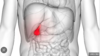

Referred pain to these dermatomes is likely to be cause by which pathology? [1]

Slipped disc

Referred pain to this area is likely to be caused by pain from where else? [1]

**Hip pain** -- radiates to knee

Where might pain from this organ be referred to? [1]

Right shoulder